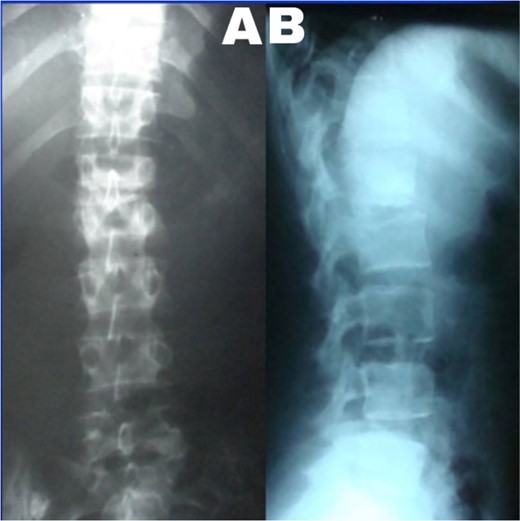

A 24-year-old farmer female was admitted to the Department of Neurosurgery with low back pain, no fever, cough, motor deficit, or any symptoms. Medical, surgical, family histories and physical examinations were unremarkable. The laboratory findings showed a white cell count of 9.8 × 103/μL, C-reactive protein concentrations of 20, erythrocyte sedimentation rate of 50 mm/1 h, 90 mm/2 h and tuberculin skin test was positive. X-ray films showed the collapse of the L1, L2 vertebrae, and L1–2 intervertebral space (Fig. 1). An abscess was observed at the L1–L2 vertebral level in lumbar magnetic resonance imaging (MRI) (Fig. 2). Chest X-rays and Sputum smear were negative. The patient was treated with anti-TB treatment (Isoniazid, Rifampicin, Ethambutol, Pyrazinamide) due to spinal TB findings on MRI (Fig. 3). After 40 days, the patient was diagnosed with grade 1/5 lower limb weakness, and bladder and bowel dysfunction, with no impairment in sensation, which predicts spinal infection. MRI confirmed these abnormalities and showed typical findings such as vertebral endplate destruction, bone marrow and disk signal abnormalities, and paravertebral or epidural abscesses (Fig. 3). Due to clinical manifestations and MRI spinal TB findings (Fig. 3), the patient underwent surgical debridement, interbody fusion and internal fixation with fibular autografting and supplemental posterior spinal stabilisation using a posterior-only approach. On post-operative follow-up, the treatment continued for 9 months, in addition to physical therapy for lower limb weakness. In the end, the patient returned to full motion with grade 5/5 in the lower limb, normal sensation, and no bladder or bowel incontinence. No recurrence was observed in the grafting area. Radiologically 2, 6 and 12 months, 14 years’ post-operation, the patient had achieved full bony graft spinal fusion (Figs 4–6).

(A) Lumbar spine X-ray, anteroposterior view showed the collapse of the L1–2 intervertebral space. (B) Lumbar spine X-ray and lateral view showed L2 superior endplate erosion.